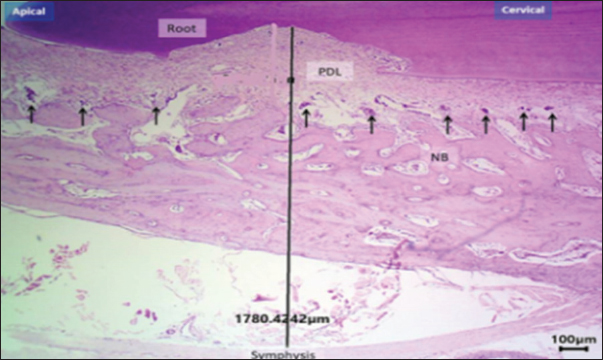

Based on the histomorphometric findings, exogen treatment markedly enhanced bone-forming activity, as evidenced by a statistically significant increase in osteoblast count at both day 10 and 20 compared with the control group (p < 0.01), indicating accelerated bone formation. In contrast, osteoclast count was significantly reduced at day 20 (p < 0.05), reflecting suppression of bone resorption. Vascular density showed a consistent and significant increase across all post-removal time points (p < 0.01), providing a more favorable blood supply for bone and periodontal tissue healing. Additionally, PDL width was narrower in the Exogen group by day 20, suggesting enhanced tooth stability after orthodontic appliance removal. Representative histological sections at day 10 are shown in Figures 7 and 8.

Fig. 7. Histological section of the exogen-treated group at day 10 showing a broad zone of newly formed bone (NB) with aligned osteoblasts (arrows). H&E stain, 40×, scale bar=100 μm.

Fig. 8. Histological section at day 10 (non-Exogen group) showing multiple blood vessels (BV) within newly formed bone (NB). H&E stain, 40×, scale bar=100 μm.

This pattern of results translates into accelerated healing of bone and periodontal tissues with an improved vascular environment, supporting the hypothesis that LIPUS can reduce post-treatment tooth relapse and promote long-term stability (Fig. 9a and b). New bone surface distribution is demonstrated in Figure 10.

Fig. 10. H&E –stained sections representing new bone surface area in control and exogen groups along cervical and apical lines at day 0. H&E, 100×, scale bar=100 μm.